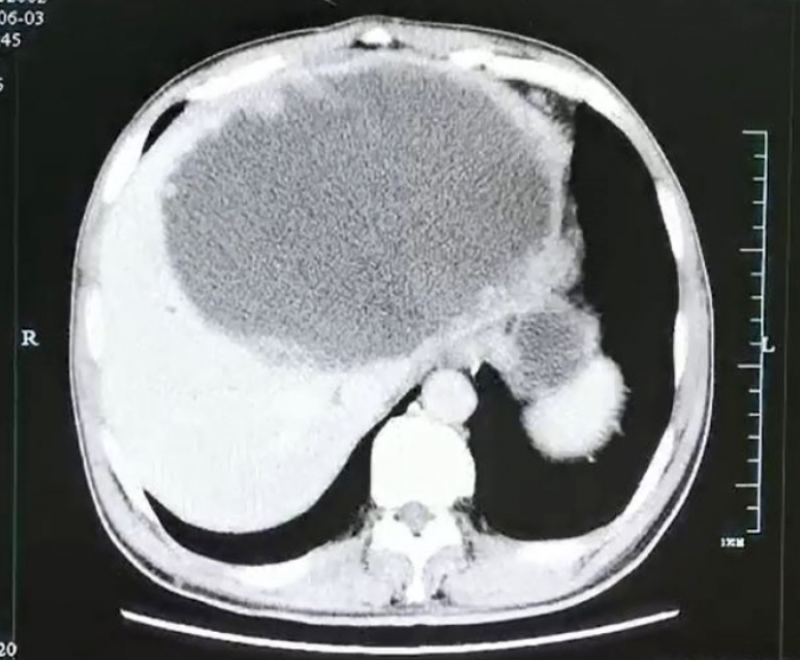

ct,等结果出来后我们都吓了一跳,患者的肝脏内竟然有一个超大的"脓球"

大脓球达到19cm×18cm×12cm大小.